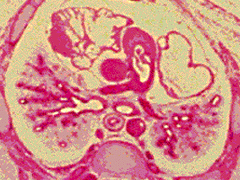

D4:

R primary bronchus (torn) and R superior lobe

bronchus. L primary bronchus. L, R pulmonary

arteries. Ribs joining to sternum.